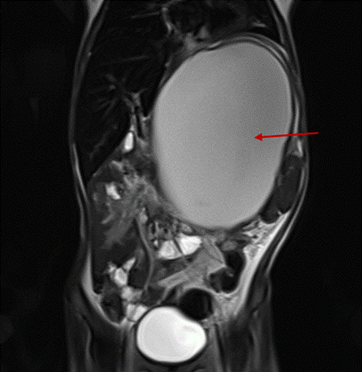

患儿腹部MRI,可见左腹部巨大的胰腺假性囊肿(箭头所指)

在儿科消化专业门诊就诊后,夏夏被紧急收入儿科普通病房,很快做了腹部核磁共振检查,可以看到她小小的腹腔被胰腺部位的巨大囊肿挤占了大半,16cm×12cm的大囊肿挤压了其他器官,影响了夏夏的进食,甚至挤压了肺部空间,影响到了呼吸和心跳。她皮下脂肪薄,重度营养不良。为了改善营养状态,除了给予患儿肠内营养,儿科还联合介入血管外科,由张龙副主任医师为夏夏进行了经皮穿刺深静脉置管,留置了PICC输注肠外营养液改善营养状态。